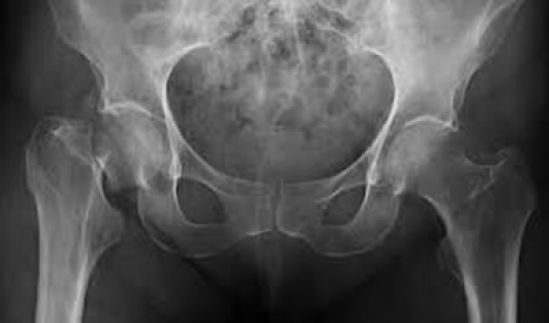

Según cifras del Instituto Mexicano del Seguro Social, 10 millones de mexicanos sufren osteoporosis, lo que significa un aumento de fracturas. De las personas que padecen la enfermedad, el 18% son mujeres de entre 35 y 65 años. Además, afirman datos oficiales, entre las mujeres mayores de 50 años el riesgo de muerte por fractura de cadera es tan grave como el de muerte por cáncer, y 8% de mujeres y 5% de hombres tienen probabilidades de sufrir una fractura de cadera después de esa edad.

Otro dato importante es que entre las mujeres el riesgo de fracturas es de 2 a 3 veces mayor que en los hombres, por lo que 75% de esas lesiones por osteoporosis las padecen ellas. Al respecto, en su blog la empresa de lácteos Lyncott, basada en especialistas, recomienda para las mujeres entre los 19 y 49 años un aporte diario de 1000 mg de calcio acompañado de 400 a 1000 UI, mientras que para las mayores de esa edad dosis de 1200 mg y de 800 a 2 mil UI, respectivamente.